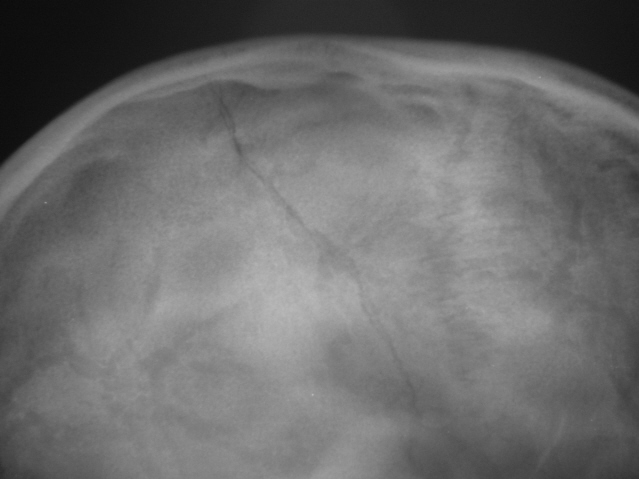

Пациент в ургентном порядке, после ДТП был доставлен в ЦРБ в ночное время. Был вызван "ургентный лаборант" для рентгенографии черепа. Пациент без сознания. С учетом состояния пациента рентгенография произведена в нестандартных проекциях - "задняя прямая".

Линейный перелом костей крыши черепа, возможно с переходом на основание. Вот только не понятно есть или нет импрессионный перелом височной кости, а ещё больше похоже на наличие пневмоцефалии.

Линейный перелом с переходом на основание - дно средней черепной ямки. Сейчас вопрос о пирамидке и орбите не принципиальный. Главный вопрос нет ли внутричерпной гематомы. Если больной выйдет из тяжелого состояние, и встанут экспертные вопросы можно сделать Стенверс при потере слуха, Майер при кровотечении из уха. Насчет стенки орбиты - наличие перелома сомнительно, явно не видно. Также можно доснять при улучшении состояния. Судя по всему это молодой человек. Сколько лет?

Вижу только линию перелома височной и теменной костей, высока вероятность перехода на основание, остальное - домыслы и сомнения.